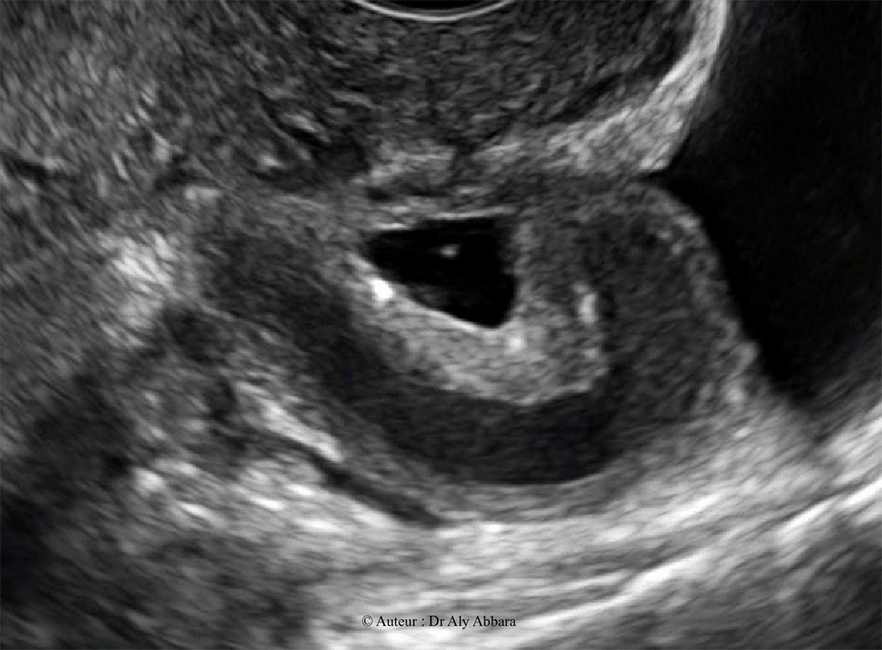

Salpingite chronique - Hydrosalpinx - Echographie

Image animée montrant l'aspect échographique d'une

salpingite chronique caractérisée par l'épaississement des parois tubaires et l'obstruction

de l'extrémité distale de la trompe à l'origine de la formation d'un hydrosalpinx